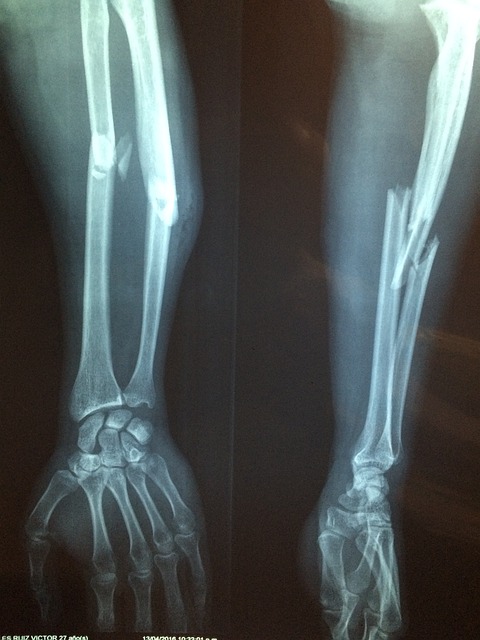

- X-레이: 슬개골과 대퇴골 사이의 정렬 상태를 평가하고, 뼈의 구조적 문제가 있는지 확인합니다. 그러나 X-레이는 연골 자체는 보여주지 않습니다.